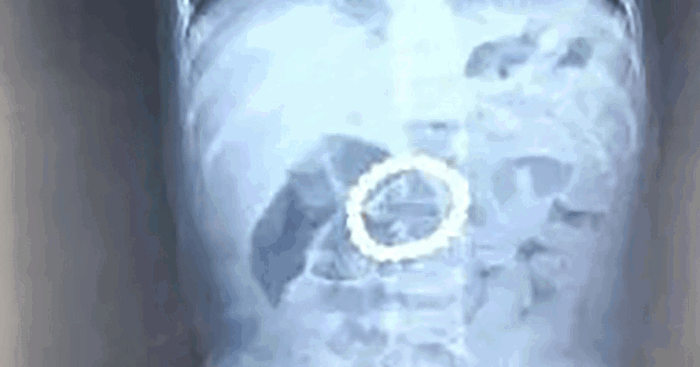

They brought him to their local hospital in Hebei Province, China, where an x-ray revealed a mass of small magnetic beads in his stomach. However, doctors were unable to remove the magnets.

Surgeons at Beijing Childrens Hospital removed a ring of 21 magnetic balls from a toddlers stomach. Photo: Weibo

Image source: Weibo

Doctors concluded the magnetic beads — 21 in total — were in the boy’s stomach for four to five days. During the operation, doctors managed to remove all the magnetic beads, which had already formed a ring inside the toddler’s stomach.

The clumping together could have caused serious scarring. Had they not removed the beads when they did, they could have even pierced through his organs.